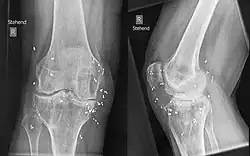

Bei der klassischen Goldstückchenimplantation werden kleine zylindrische Segmente (etwa 1 bis 3 Millimeter lang) aus 24-karätigem Golddraht von 1 Millimeter Durchmesser gelenknah implantiert. Die Segmente werden beim Menschen in lokaler Betäubung, beim Tier in Sedation mittels einer Hohlnadel rund um das Gelenk eingebracht. Die Stücke liegen außen an der Gelenkkapsel, nicht im Gelenk. Die Anzahl schwankt je nach Gelenk zwischen 10 und 50 Stück.

In der Tiermedizin wird die Goldimplantation zum Beispiel angewandt bei Hüftdysplasien, Osteochondrosis, Osteochondrosis dissecans der Schulter, Arthritis des Ellenbogens und des Knies, Spondylose des Rückens, Ankylosen, Cauda-equina-Kompressionssyndrom, Wobbler-Syndrom und epileptischen Anfällen von Hunden. Vor der Behandlung werden neben dem Einsatz von Röntgentechnik üblicherweise eine Gangbildanalyse und Triggerpunktuntersuchung durchgeführt. Eingenommene schmerzarme Schonhaltungen verändern den Bewegungsablauf und geben zusammen mit Bewegungsschwächen (Lahmheiten) Aufschluss über den Problembereich.